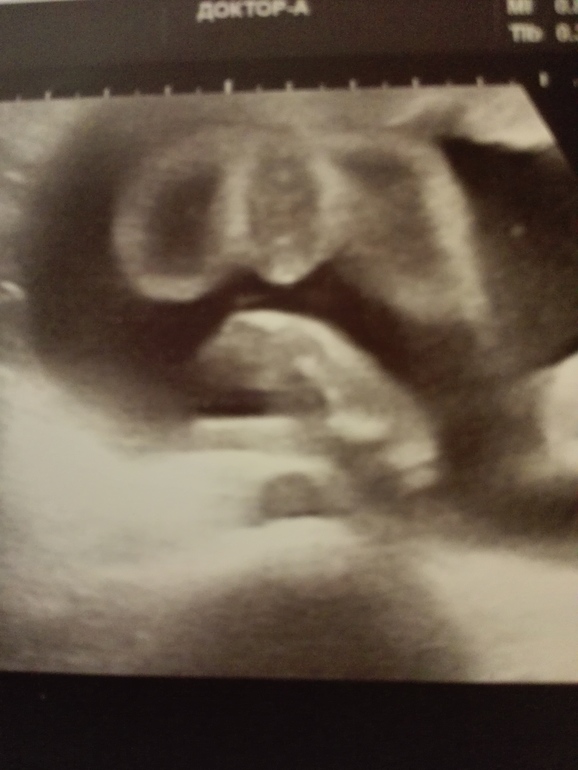

Фото узи

Вопросы про УЗИ, обследования и анализы: что, где, как, когда?Девченки на сроке 22-23 недели ходила на узи узнать пол ребенка,сказали что девочка,муж все равно думает,что мальчик. Кто разбирается посмотрите)))

Девчуля же!!! Если б пацан был и так же сидел на попе, то и писюн торчал бы а не только яички))))

там попка и ножки вытянуты..на попке сидит, а где стрелочка там пирожок =))

Ой,наверное девочка всеж,у нас мальчик по узи конкретно так выглядит. И фаберже и писюн, а тут ничего похожего нет.